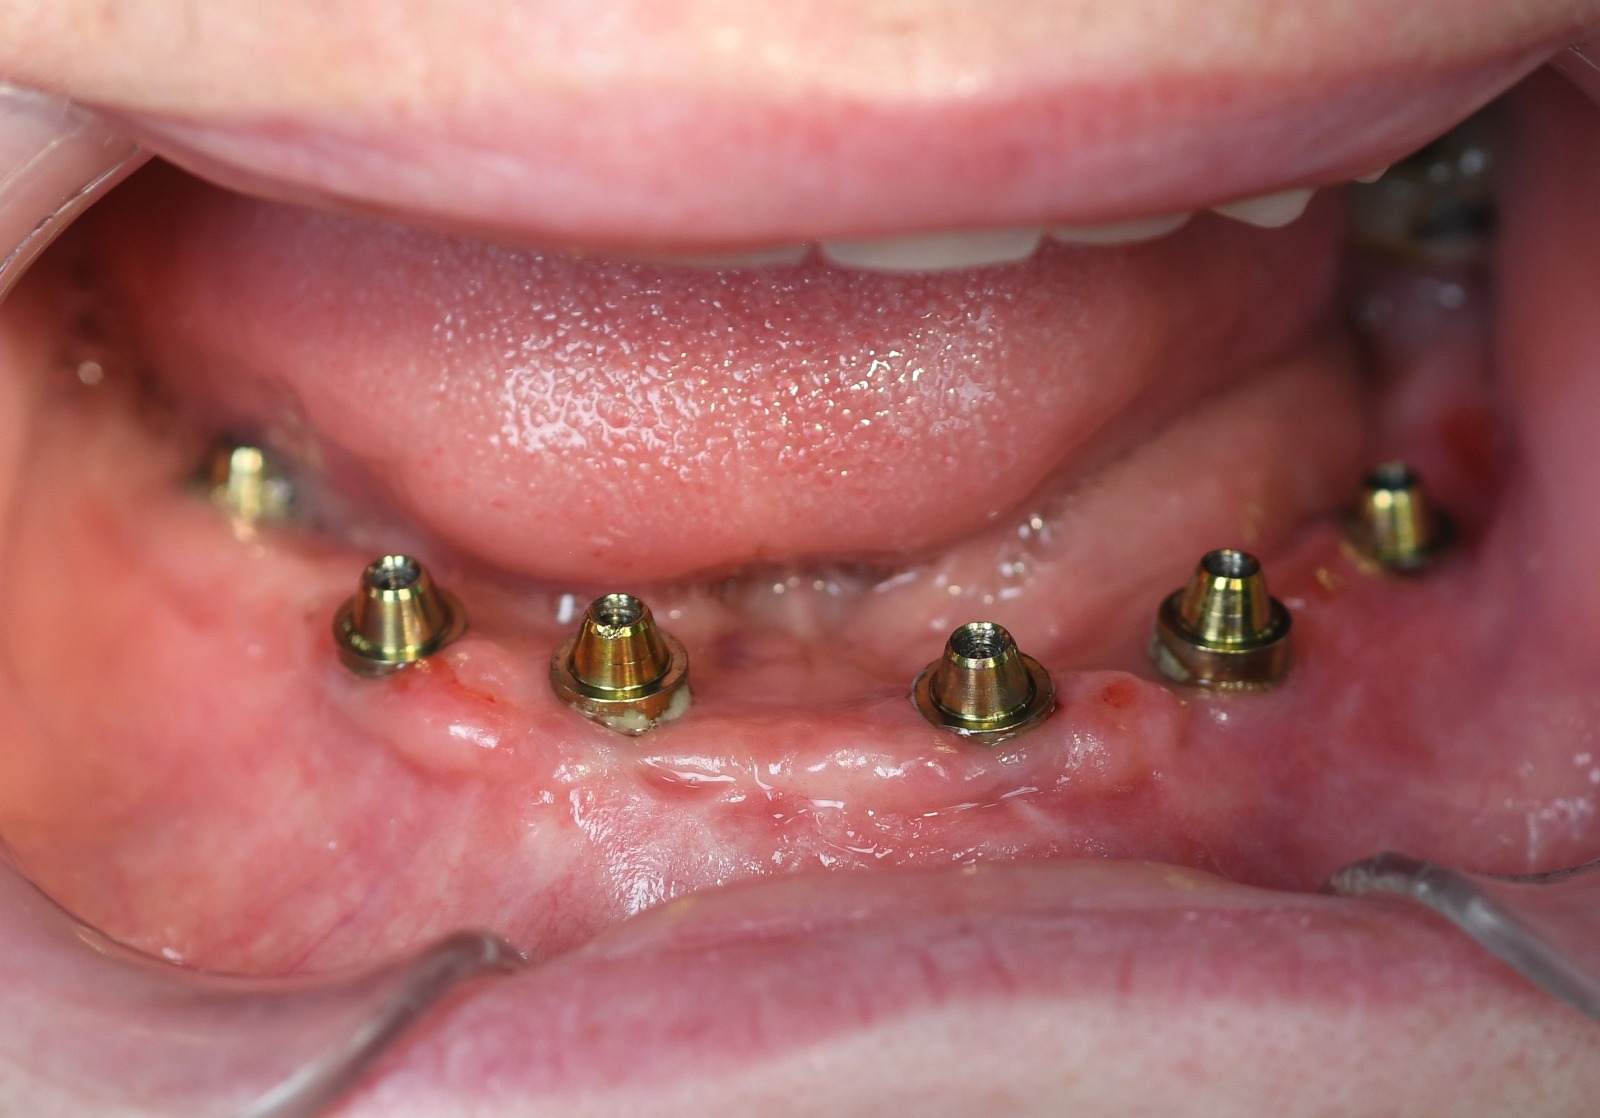

All-on-6 Restoration of Mandible clinical case